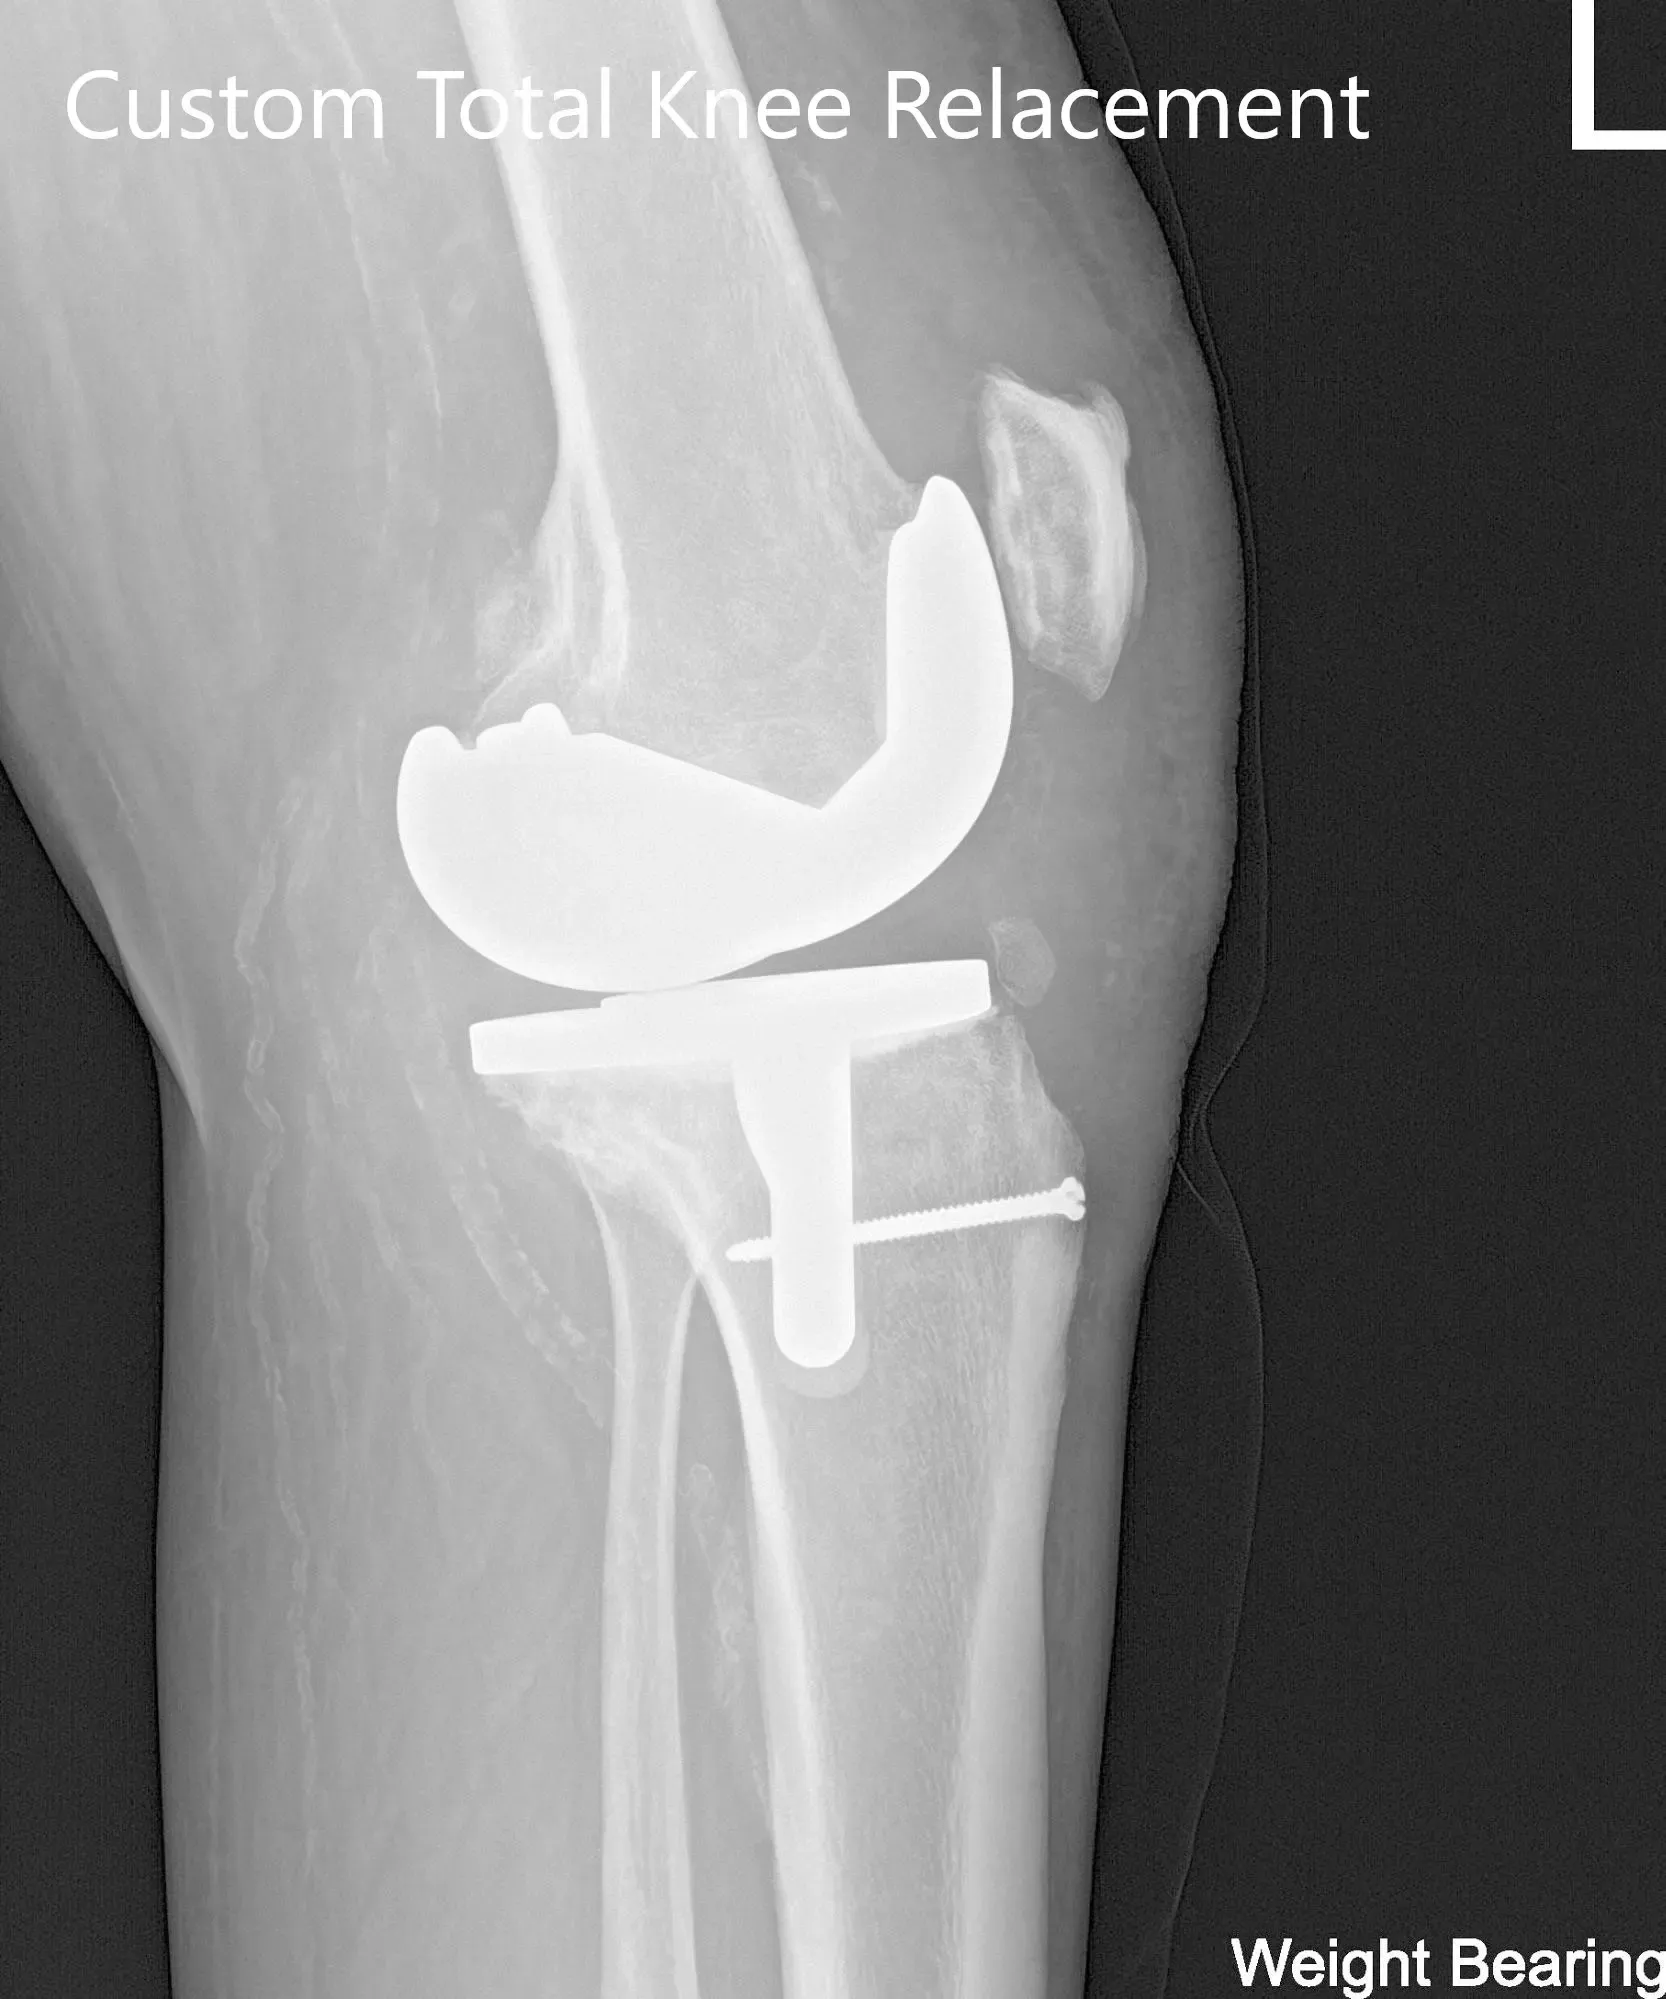

El paciente se sometió a una tomografía computarizada preoperatoria unas semanas antes de la cirugía. Los datos se utilizaron para crear instrumentos impresos en 3D personalizados e implantes únicos específicos para cada paciente. Los datos se utilizaron para crear un plan preoperatorio que detallaba cortes óseos y desplazamientos femorales. Los implantes personalizados aseguran que se preserve la mayor cantidad posible de hueso y que se recree la biomecánica biológica.

Implante – Artroplastia total de rodilla izquierda usando fémur personalizado, tibia, rótula y polietileno de 6 mm personalizados

Radiografía postoperatoria de la rodilla izquierda que mostró visión AP y lateral